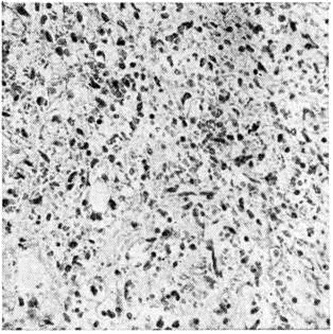

Рис. 3.

Микропрепарат ткани лёгкого при остром миелобластном лейкозе: лейкозная инфильтрация по ходу межальвеолярных перегородок (1) и периваскулярно (2), скопление бластных клеток в просветах альвеол (3). Окраска гематоксилин-эозином; ×80. Рис. 4. Микропрепарат костного мозга при остром мегакариобластном лейкозе: скопления атипичных мегакариоцитов указаны стрелками. Окраска гематоксилин-эозином; ×400.

Острый миелобластный лейкоз в развёрнутой стадии болезни характеризуется выраженной лейкозной инфильтрацией костного мозга и других органов. В печени лейкозные разрастания локализуются в синусоидных капиллярах и в области портальных трактов. Аналогичное расположение инфильтратов имеется и при других более редких формах острого Лейкозы (монобластном, миеломонобластном, недифференцируемом, промиелоцитарном и другие), поэтому данный признак не может служить основанием для разграничения форм острого Лейкозы В лёгких лейкозная инфильтрация обычно выявляется по ходу межальвеолярных перегородок с выходом бластных клеток в просветы альвеол (рисунок 3), возможна локализация и в окружности бронхов, сосудов, междольковых перегородках. У детей при этой форме Лейкозы лейкозные разрастания в вилочковой железе располагаются в соединительнотканных прослойках, сдавливают дольки, что сопровождается увеличением количества аргирофильных волокон. У взрослых типично развитие множественных узлов в надкостнице плоских и трубчатых костей, почках, печени, половых железах, жировой клетчатке (подкожной, ретробульбарной, клетчатке большого сальника и малого таза), иногда в коже, конъюнктиве, твёрдой мозговой оболочке и костном мозге. В ряде случаев в области опухолевых узлов и системных поражений имеется зелёное окрашивание ткани (хлоролейкоз). Аналогичные изменения могут выявляться и при Лейкозы у детей.